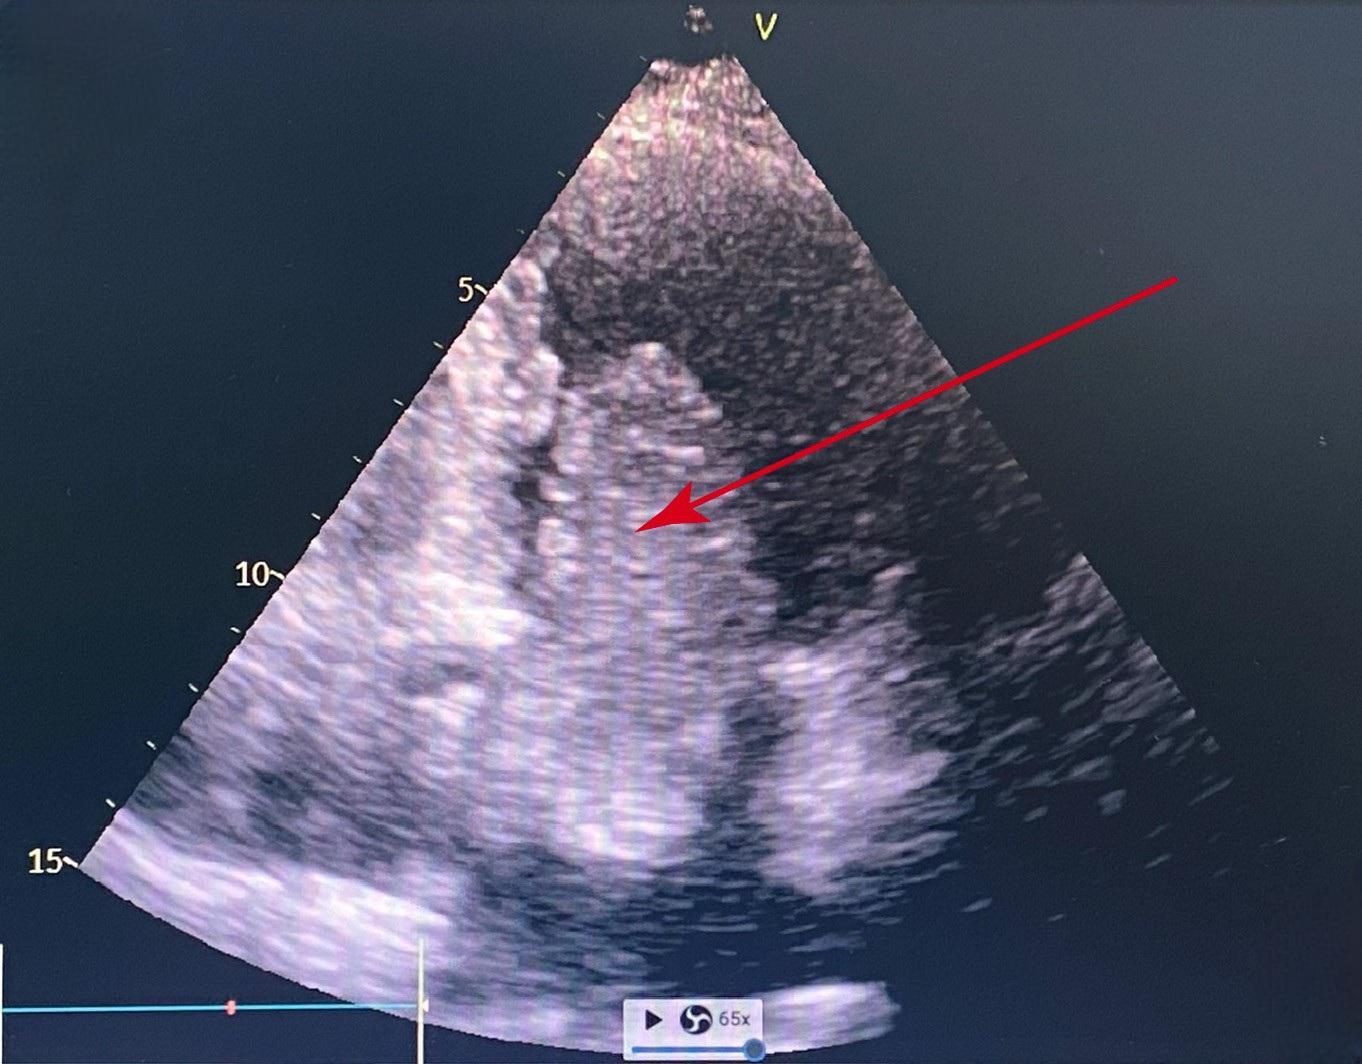

Doctor Pham Thuc Minh Thuy, from the Cardiology Center, reported that the echocardiogram showed an 11x4 cm tumor (suspected myxoma) in the left atrium. The tumor consisted of three connected lobes and moved across the mitral valve.

Pre-operative ultrasound shows the left atrial myxoma passing through the mitral valve to the apex of the heart. Photo: Tam Anh General Hospital

Doctor Tran Thuc Khang, Deputy Head of Cardiothoracic Surgery at the Cardiology Center, surgically removed the gelatinous tumor attached to the interatrial septum. He performed a wide excision around the base of the tumor to prevent recurrence, checked the mitral valve, and reconstructed the interatrial septum. Post-operative pathology confirmed the tumor was benign. A week after surgery, Huong had recovered, resumed normal activities, and no longer experienced fatigue. She continues to receive post-operative support and treatment.